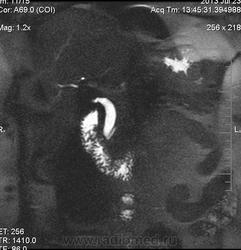

очень характерная картина для метастаза рака яичника, к сожалению.

Не могу достоверно определить локализацию метастаза брюшной полости, вероятно в лимф. узел с инвазией оободочной кишки. Рецидив С-r левого яичника думаю, что с инфильтацией левой стенки прямой кишки и культи влагалища, вторичная лимфаденопатия л/у малого таза. каликопиелоуретероэктазия (инвазия нижних отделов левого мочеточника?) Холедох широковат, но желтухи по внешнему виду нет.

Прорастание левого мочеточника рецидивной опухолью есть 100%, метастаз в большой сальник характерен для рака яичников, как и сигнальные характеристики его. Культя в данном случае шейки матки.

Большое спасибо. По поводу стриктуры холедоха мучают сомнения.